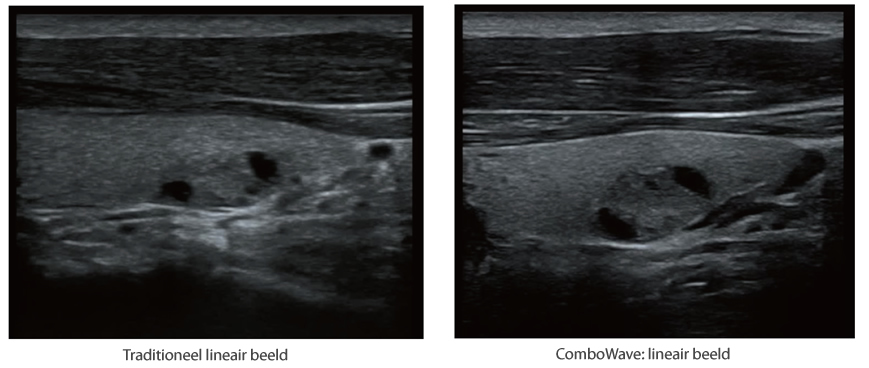

ComboWave transducers

In tegenstelling tot traditionele transducers gebruiken de ComboWave-transducers een nieuw type samengesteld pi?zo-elektrisch materiaal om het akoestische spectrum drastisch te optimaliseren en de akoestische impedantie te verminderen. De lineaire transducers van ComboWave, die verder zijn ge?ntegreerd met de unieke 3T-technologie van Mindray, stellen u in staat uitstekende prestaties te ervaren met een extreem hoge beeldresolutie en uniformiteit in de schildklier, borst, vaten en meer.